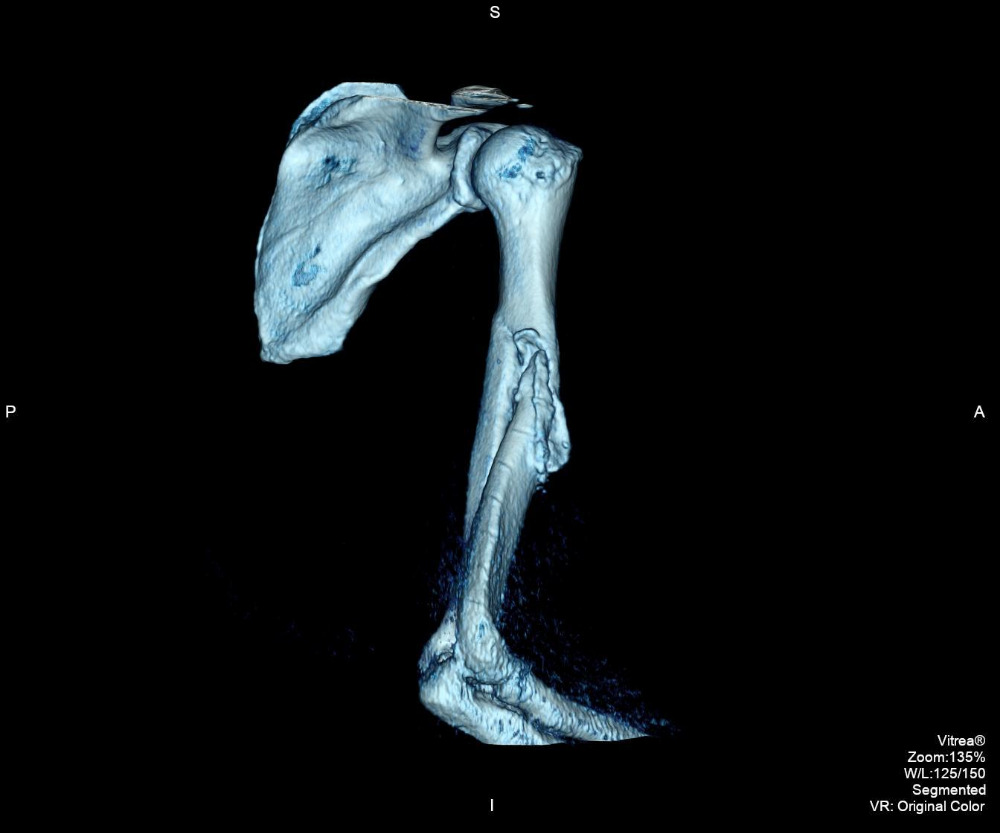

I had my surgery on September 13th, 2016. According to the doctor, it was" very, VERY BAD!" He had to find the nerve buried within the fracture. Carefully move it out of the way before he could clean up the debris of the broken bones. The bicep muscle was caught between the fractures. He had to recut the bone to straighten it out, place a twelve inch long, metal plate with a dozen screws, to hold it all in place. The over two year wait didnt do me any favors. I now have a long healing process and eventually physical therapy. Meanwhile, I no longer have living benefits and I desperately need your continued help. I need to raise a minimum of $4,000 to survive through January 2017. Anything will help, I would be very grateful. Thank you.

I found a good worker comp lawyer and a real ortho specialist. On March 31st, 2015 ( my 56th birthday) I saw the doctor. The X-ray was taken. He took one look and said I needed surgery. It would never heal on its own. He classified it as a "disastrous break." In May, I had an appointment with another specialist. He only worked on upper extremities. Yup, needs surgery, with a rod and some screws and other things. My surgery was set in September of 2015. I would never have 100% use of my right arm, ever again. He didn't know how much damage the break caused, until he cut my arm open. Then a nurse took my blood pressure. It was sky high, 198/110. The doctor nealy fell over and wondered how I was still standing. Now, I needed BP meds and other tests. The insurance company denied 99% of every request. I failed the pre-op and the surgery was cancelled.